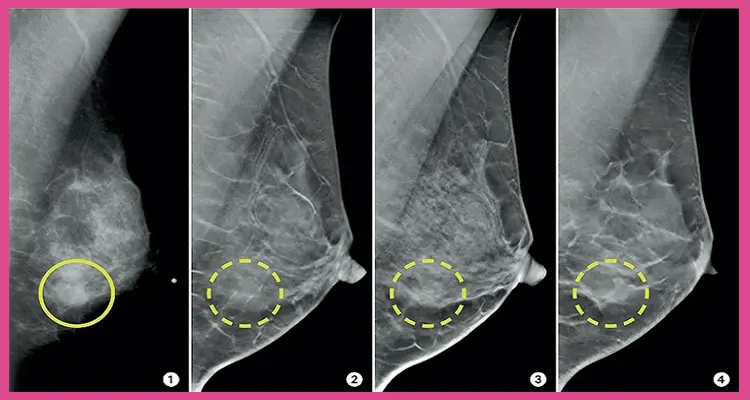

دستگاه ماموگرام دارای سه نوع دیجیتال و دستگاه CAD و DBT میباشد. در دستگاه های دیجیتال ماموگرام، اشعه ایکس با بافت های بدن برخورد کرده و تصاویر دقیقی را بعد از بررسی وضعیت سینه ها نمایش خواهد داد. دستگاه cad در ماموگرافی تمامی توده های موجود را با رنگ تیره تر در تصاویر نشان میدهد به گونه ای که انگار رسوب ایجاد شده است. در روش DBT که همان ماموگرافی سه بعدی میباشد، از سینه تصاویری سه بعدی تهیه میکند که فایده آن در همین است که دور تا دور بافت سینه به خوبی نمایش داده میشود. با استفاده از تمامی این تکنیک ها، انواع ناهنجاری پستان با دقت بیشتری مورد بررسی قرار میگیرد. امروزه بیشتر متخصصان و جراحان پستان ماموگرافی دیجیتال را تجویز میکنند و با آن به بررسی بافت ینه میپردازند.

سرطان سینه و مرگ در اثر آن، آمار زیادی را میان بانوان به خود اختصاص داده است و از رایج ترین انواع سرطان میباشد. ماموگرافی معمولا از سن 40 سالگی انجام میشد اما با پایین تر اومدن سن سرطان میان افراد، بهتر است تا این روش از سن 35 سالگی به طور مرتب انجام شود. سرطان سینه با وجود و انجام این روش از نظر آماری کاهش بسیاری پیدا میکند. توجه داشته باشید که ماموگرافی هیچ کمکی به جلوگیری از این بیماری ناخوشایند نداشته و فقط قابلیت تشخیص آن را دارد. لازم به ذکر است که با تشخیص سریع تومور و کیست های بدخیم و سرطانی، بیماری سرطان زودتر شناخته میشود و اقدامات درمانی لازم به موقع صورت میگیرد.